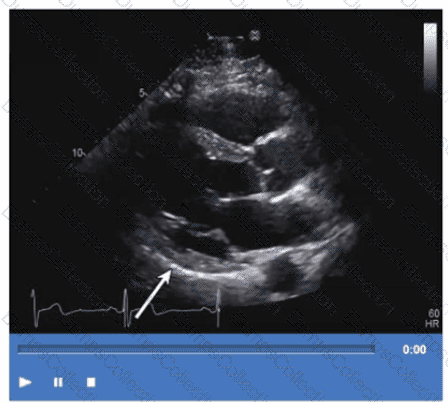

Which wall is indicated by the arrow on this video?